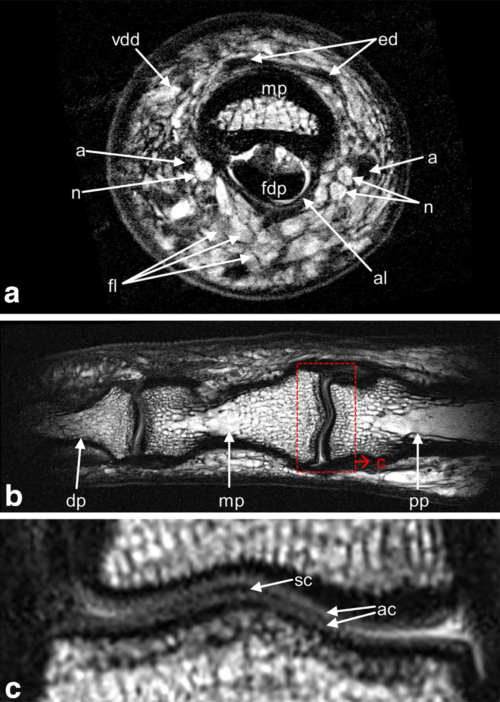

Unsere selbst entwickelten hochempfindlichen Hochfrequenzspulen ermöglichen die Mikrobildgebung menschlicher Extremitäten in vivo an einem Ultrahochfeld-MR-Scanner (7T). Mit einer speziellen Fingerspule ist es möglich, die inneren Strukturen des menschlichen Fingers in vivo in patientengerechter Messzeit darzustellen. Verschiedene anatomische Merkmale wie Knochen und Knochenmark, Sehnen und Ringbänder, Knorpel, Arterien und Venen, Nerven und Vater-Pacinische Tastkörperchen können mit einer Pixelgröße von etwa 80×80 µm2 dargestellt werden. Dies kann zur Diagnose und Behandlungsüberwachung bei Pathologien dienen, die von entzündlichen oder erosiven Gelenkerkrankungen über Verletzungen von Sehnen und Bändern bis hin zu Nerven- oder Gefäßstörungen im Finger reichen (Laistler et al. Magn Reson Med 79:588–592, 2018).